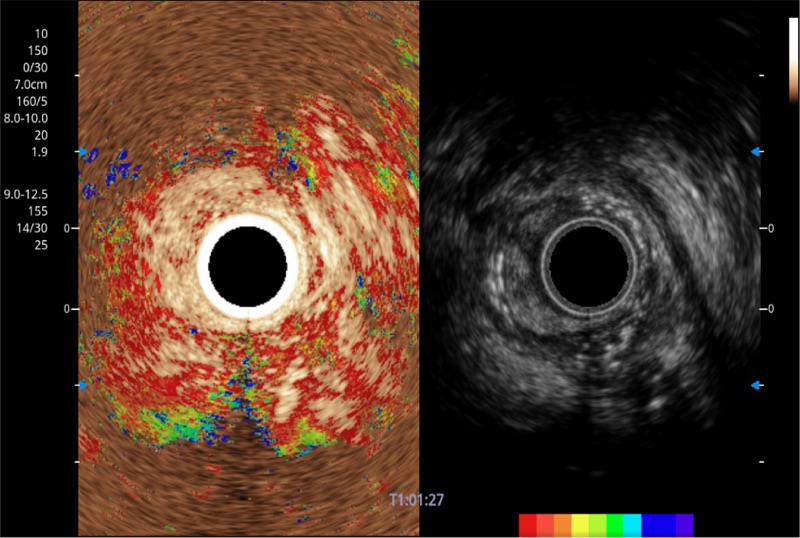

• 伪彩(Chroma)

可人为将灰阶图像转变成彩色的显示方式,增强人眼对于不同回声强度的敏感度,主观上增加了图像分辨率

• 微米成像 (μ-Scan)

微米成像技术提升了对组织斑点噪声信号的抑制能力,并进一步强化边界信息,从而获得信噪比更优、边界更清楚锐利的图像